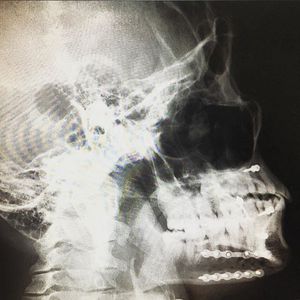

Happy traumatuesday πŸ˜‚can you see the plates and screws? After surgically repairing jaw fractures , it is important to obtain post-operative X-rays to evaluate and verify the positioning of the jaws and the newly placed hardware πŸ’ŽπŸ’βŒšοΈπŸ˜Ž